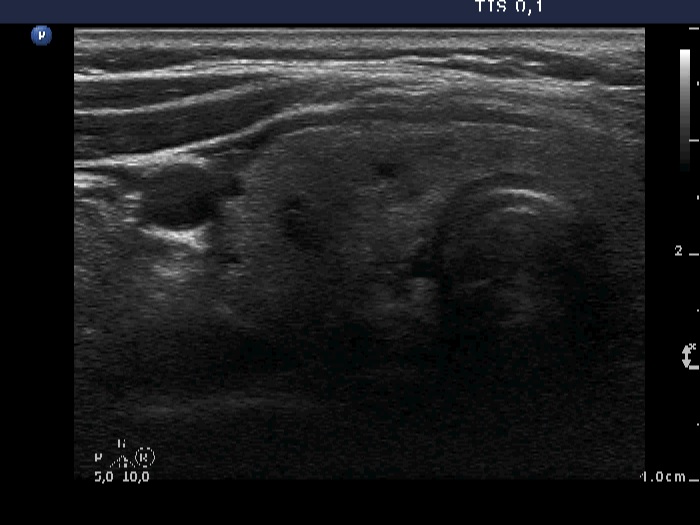

Ultrasonography. The thyroid was echonormal and contained several small cystic lesions. There was a relatively large nodule in the lower-dorsal part of the right lobe while multiple nodules with different echogenicity in the left lobe. The location of the right nodule raised the possibility of parathyroid origin.